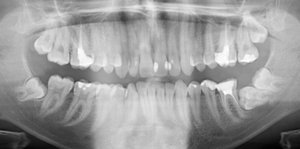

У меня два нижних зуба мудрости выросли неправильно, т.е. горизонтально, вылезли не полностью, а частично торчат. Один уже с кариесом и даже откололся.

Вообще, рекомендуется удалять ретенированные 8-е зубы по одному (максимум по два), так как это довольно длительная и сложная манипуляция. Пациенту сложно просидеть так долго с широко открытым ртом.

Таким образом, моё мнение, лучше удалять по одному, причём с перерывом в несколько недель, если зубы не беспокоят.